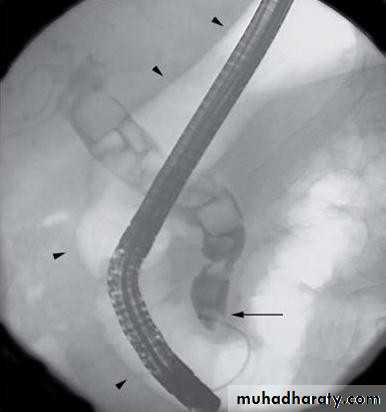

• ENDOSCOPIC RETROGRADE

• CHOLANGIOPANREATOGRAPHY (ERCP)

•  Side veiwing endoscopie

•  Cannulation of ampulla of Vater

•  Injection of contrast to visualize the bile

• ducts

•  Also bile can be taken for cytological and

• microbiological tests

•  Brushings from strictures

• ERCP